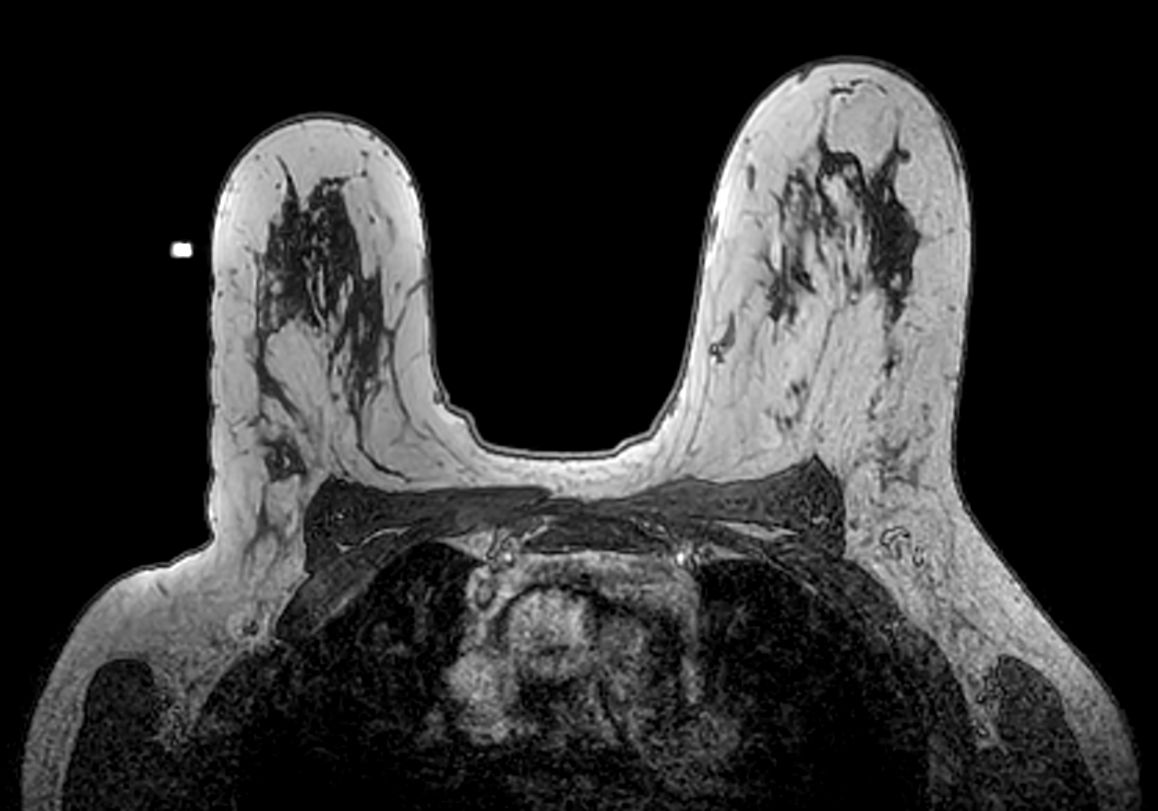

Axial 3D T2w BreastVIEW